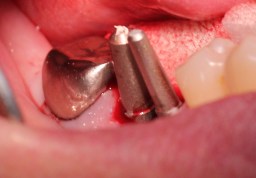

遠心に5ミリ、近心に4ミリの

インプラントを植立